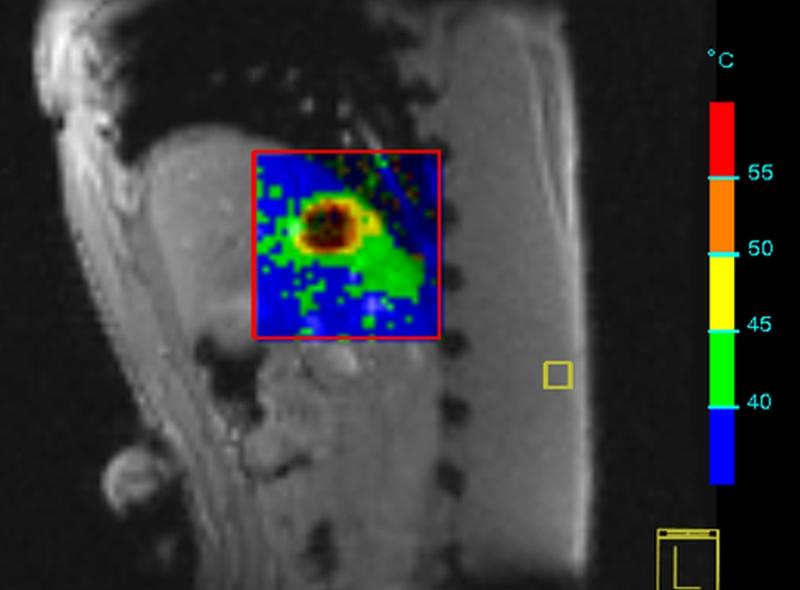

Kooperation zur Forschung in der Bildgebung

Die Medizinische Hochschule Hannover (MHH) kooperiert mit dem Forschungscampus STIMULATE (Solution Centre for Image Guided Local Therapies) in Magdeburg, der…